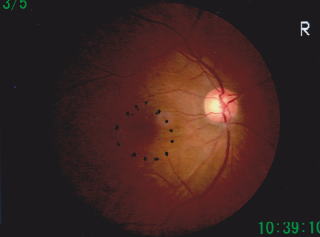

黄斑円孔、治療前   一番の原因は加齢による硝子体の変化によるものです。眼球は硝子体(しょうしたい)というゼリー状の物質で満たされています。年齢が進むとともに、この硝子体が収縮します。網膜と硝子体は接触していて、硝子体が収縮するとき、素直にぽんとはずれてくれればよいのですが、うまくはずれずに網膜に孔を開けてしまうことがあります。これが、運悪く黄斑に起きた場合、黄斑円孔が起こります。

写真は1か月前から右目が歪むと受診した患者さんの眼底写真です。黄斑部(点線・○で囲った部位)に丸く孔があいています。